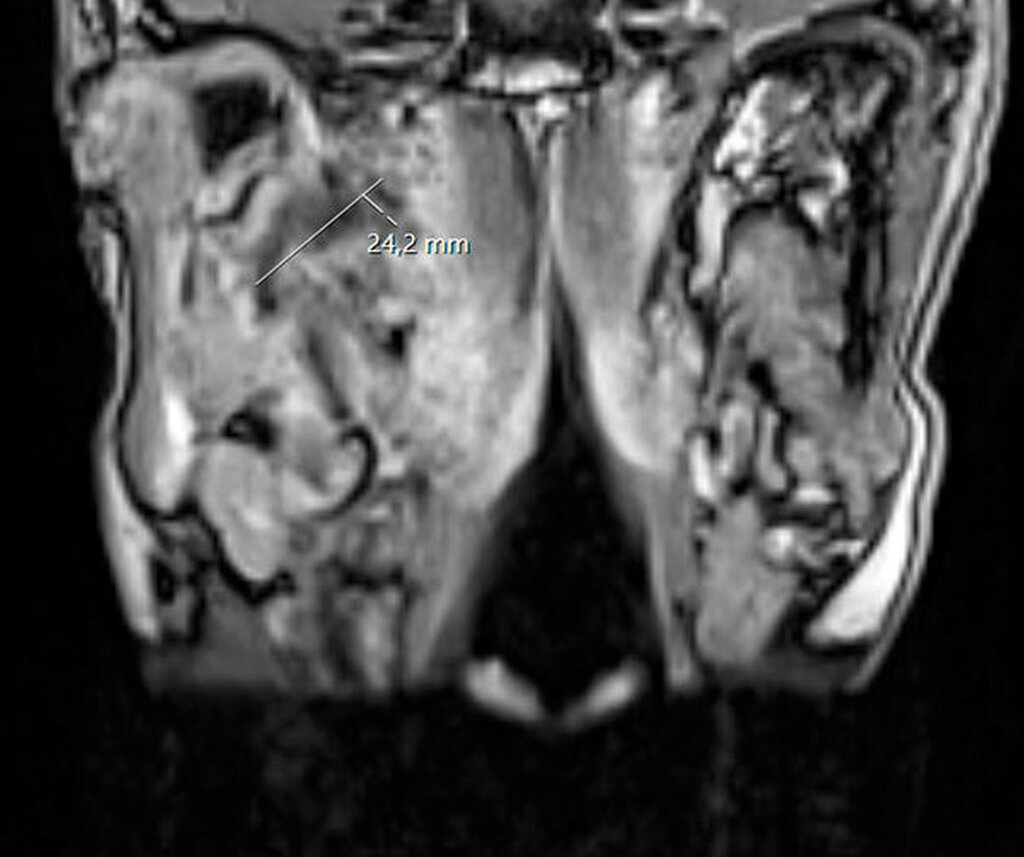

Sonografisch ließ sich weder von submandibulär noch von temporal eine klar abgrenzbare Abszessformation darstellen. Ein initial angefertigtes Labor zeigte stark erhöhte Entzündungsparameter mit einem C-reaktiven Protein von 261 mg/l (Normwert < 5 mg/l) sowie einer Leukozytose von 18/nl (Normwert 3,5–10/nl). Zur weiteren Diagnostik erfolgte die Anfertigung einer Computertomografie des Schädels mit Kontrastmittel. Hier zeigte sich eine circa 14 mm x 45 mm große, liquide Veränderung rechts im Musculus Pterygoideus mediales bis in die Glandula Parotis rechts reichend (Abbildungen 1 und 2). Aufgrund einer flauen Parenchymkontrastierung ließ sich eine Abszessformation nicht sicher ausschließen, die Befunde sprachen in Zusammenschau mit dem zeitlichen Ablauf und der stattgefundenen zahnärztlichen Behandlung jedoch in erster Linie für ein postinterventionelles Hämatom. Eine antikoagulatorische und/oder thrombozytenaggregatorische Therapie konnte ausgeschlossen werden.

Unmittelbar nach der stationären Aufnahme wurde mit der intravenösen Antibiotikatherapie, Glukokortikoidgabe und antiphlogistischen Maßnahmen begonnen. Daraufhin zeigten sich die klinischen und die laborchemischen Entzündungsparameter rückläufig. Die Mundöffnung der Patientin war bereits am Folgetag mit einer Schneidekantendistanz von 40 mm deutlich verbessert. Zur Verlaufskontrolle und Beurteilbarkeit des Weichgewebes im Bereich der Mastikatorloge wurde am zweiten Tag nach stationärer Aufnahme eine Magnetresonanztomografie des Kopfes durchgeführt. Im Vergleich zur initialen Computertomografie der Halsweichteile zeigte sich eine zunehmende Resorption der liquiden ovalären Veränderungen in der rechten Mastikatorloge (Abbildungen 3 und 4). Zum Ausschluss einer otorhinolaryngologischen Pathologie wurde die Patientin konsiliarisch in der Hals-Nasen-Ohrenheilkunde der Universitätsmedizin Mainz vorgestellt. Die Kollegen fanden keine pathologischen Auffälligkeiten, so dass bei radiologisch rückläufigem Befund von einem Hämatom ausgegangen werden konnte. Am vierten Tag nach stationärer Aufnahme konnte die Patientin die Klinik mit nahezu normwertigen Laborparametern verlassen und in die ambulante Nachsorge entlassen werden.